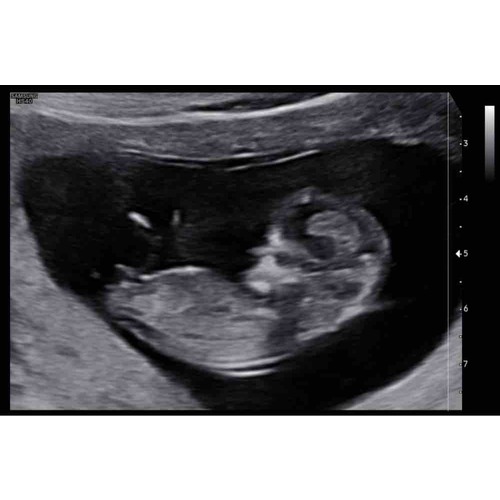

🤗 echo van 12 weken!

Meisje denk ik

Ik zie wel weer duidelijk een jongen

Hoi, dit was met de termijn echo (12 weken precies), ziet iemand hier de nub? Het echo apparaat is niet heel denderend helaas. We zijn gewoon nieuwsgierig 😊